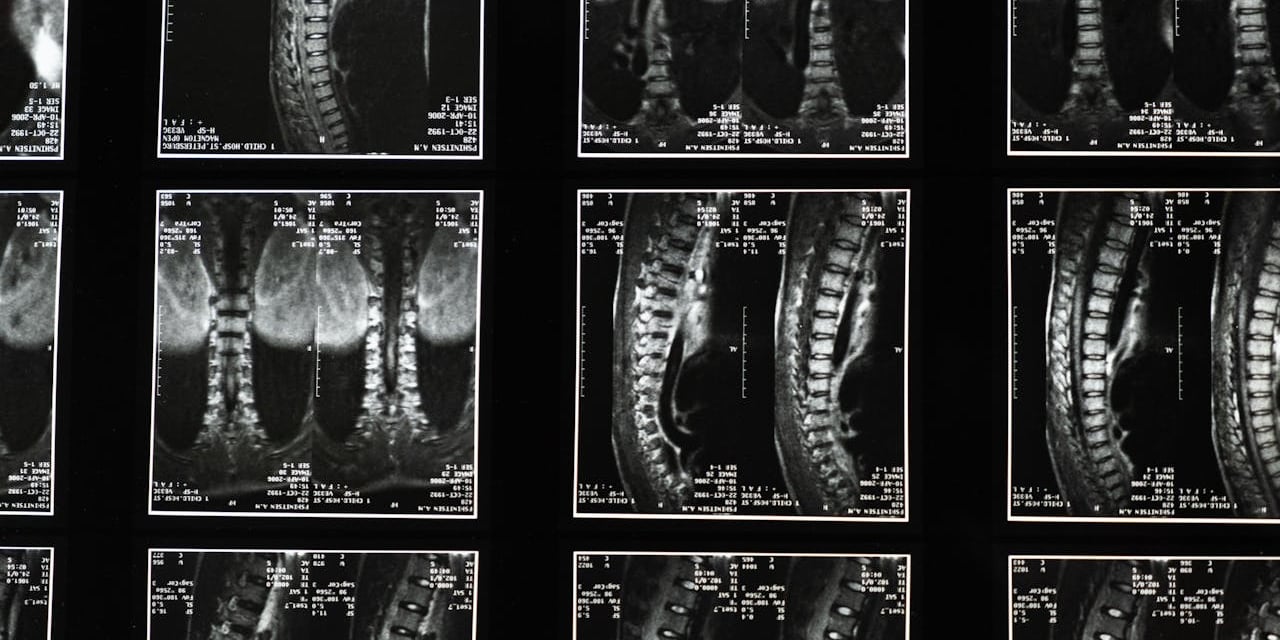

Les examens d’imagerie

Selon la situation, différents examens peuvent être prescrits :

IRM lombaire

L’IRM lombaire est l’examen de référence pour analyser les disques intervertébraux et les racines nerveuses.